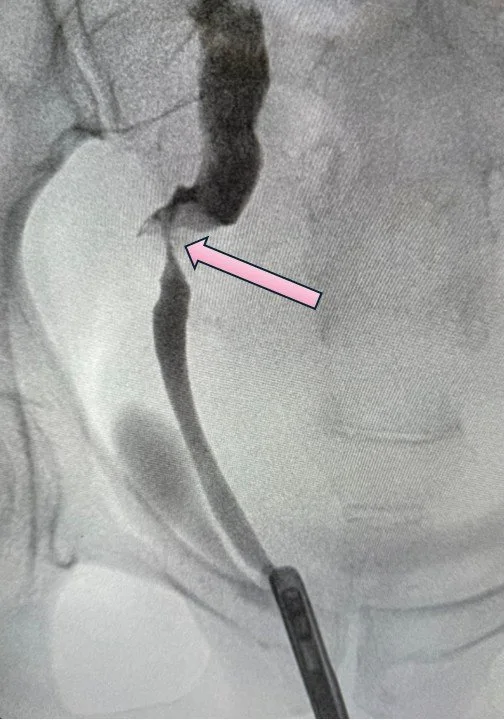

The image below is an x-ray of a patient referred to me with obstruction of the ureter which was caused by radiation therapy for cancer. The very last section of the ureter, just before it connects to the bladder, is very tight. It is another example of a distal ureteral stricture. In this case, the ureter could be directly reimplanted into the bladder without the use of a Boari flap (see case above)